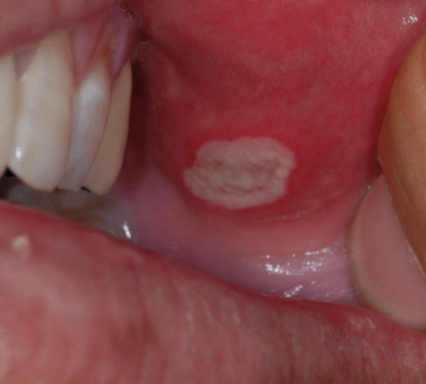

아구창이라는 것은 칸디다성 구내염을 말하는 것으로 한자로는 鵝口瘡(아구창)이라고 씁니다.

아구창은 칸디다 알비칸스라고 하는 곰팡이균에 의한 구강 감염입니다.

칸디다 알비칸스는 학명으로 Candida albicans라고 씁니다.